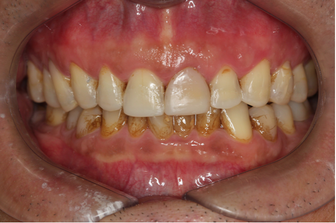

Mr NK, a 52-year-old male, presented with concerns of gradually shortening teeth and sensitivity to cold drinks. He also reported feeling self-conscious about his smile in photos. He is medically fit and has been using a night guard for his sleep-related grinding habit for the past year. Clinical examination revealed moderately worn dentition from erosion and attrition, along with mild crowding of the lower anterior incisors.

Intra-Oral Pictures (Before)

- Erosion severity: ACE Class Class III

- Reduced occlusal vertical dimension

- Mild crowding of lower anterior teeth